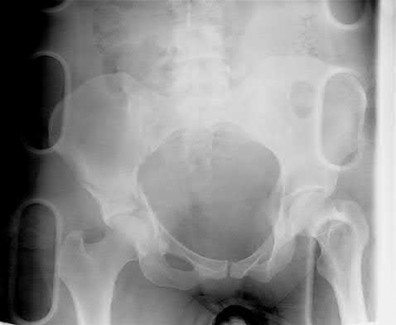

Which of the following images shows an injury pattern most consistent with a lateral compression type 3 pelvic ring injury?

Figure C is an axial CT scan of a lateral compression type 3 (LC3) pelvic ring injury.

Classically, LC3 injuries demonstrate an ipsilateral lateral compression and a contralateral APC (windswept pelvis) fracture pattern. The most common mechanism of injury in these cases is a rollover MVC or pedestrian vs. auto. LC1 injuries are characterized by an oblique or transverse ramus fracture and ipsilateral anterior sacral ala compression fracture, while LC2 injuries consist of a rami fracture and ipsilateral posterior ilium fracture dislocation (crescent fracture). While LC1 injuries can often initially be managed conservatively with protected weight-bearing and close observation, LC2 and LC3 pelvic ring injuries are almost universally operative.

Answer 1: This represents a lateral compression type 2 injury. Answer 2: This represents a lateral compression type 1 injury.

Answer 4: This represents an anterior posterior compression type 2 injury. Answer 5: This represents an anterior posterior compression type 3 injury.